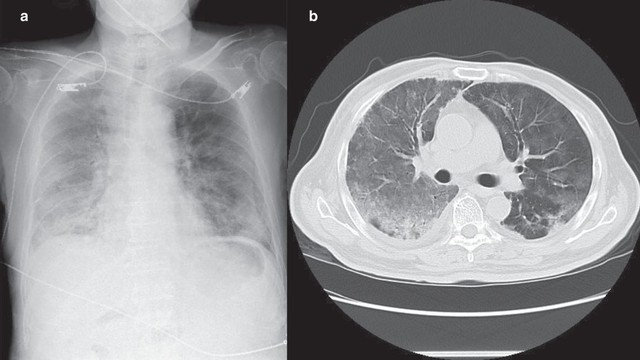

Áp xe phổi là một biến chứng hô hấp nghiêm trọng có thể đe dọa tính mạng nếu không được phát hiện và điều trị kịp thời. Bệnh thường bị nhầm lẫn với viêm phổi thông thường, khiến nhiều người chủ quan. Vậy áp xe phổi có nguy hiểm không và cần theo dõi, điều trị thế nào để giảm nguy cơ biến chứng?